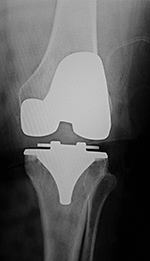

| 65 year-old woman with bilateral cruciate-retaining total knee arthroplasties (TKAs) placed in early 2009. In November 2015 routine follow-up showed bilateral aseptic loosening in both tibial components with wide periprosthetic lucencies (arrows) and varus deformity on the left. From left to right, respectively, AP radiograph of the left knee in the postoperative period, AP radiograph of the left knee 6.5 years later, lateral radiograph of the left knee in the postoperative period, and lateral radiograph of the left knee 6.5 years later. Images courtesy Laura H Lee, MD. |